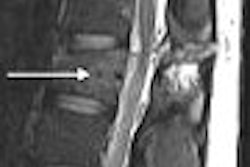

In our previous Insider, we looked at the value of MRI and ultrasound for assessing tenosynovitis, skier's thumb, and vascular flow. Today's Insider Exclusive article offers a different perspective on wrist imaging -- MR arthrography for triangular fibrocartilage tears and instability. Click here to learn more.